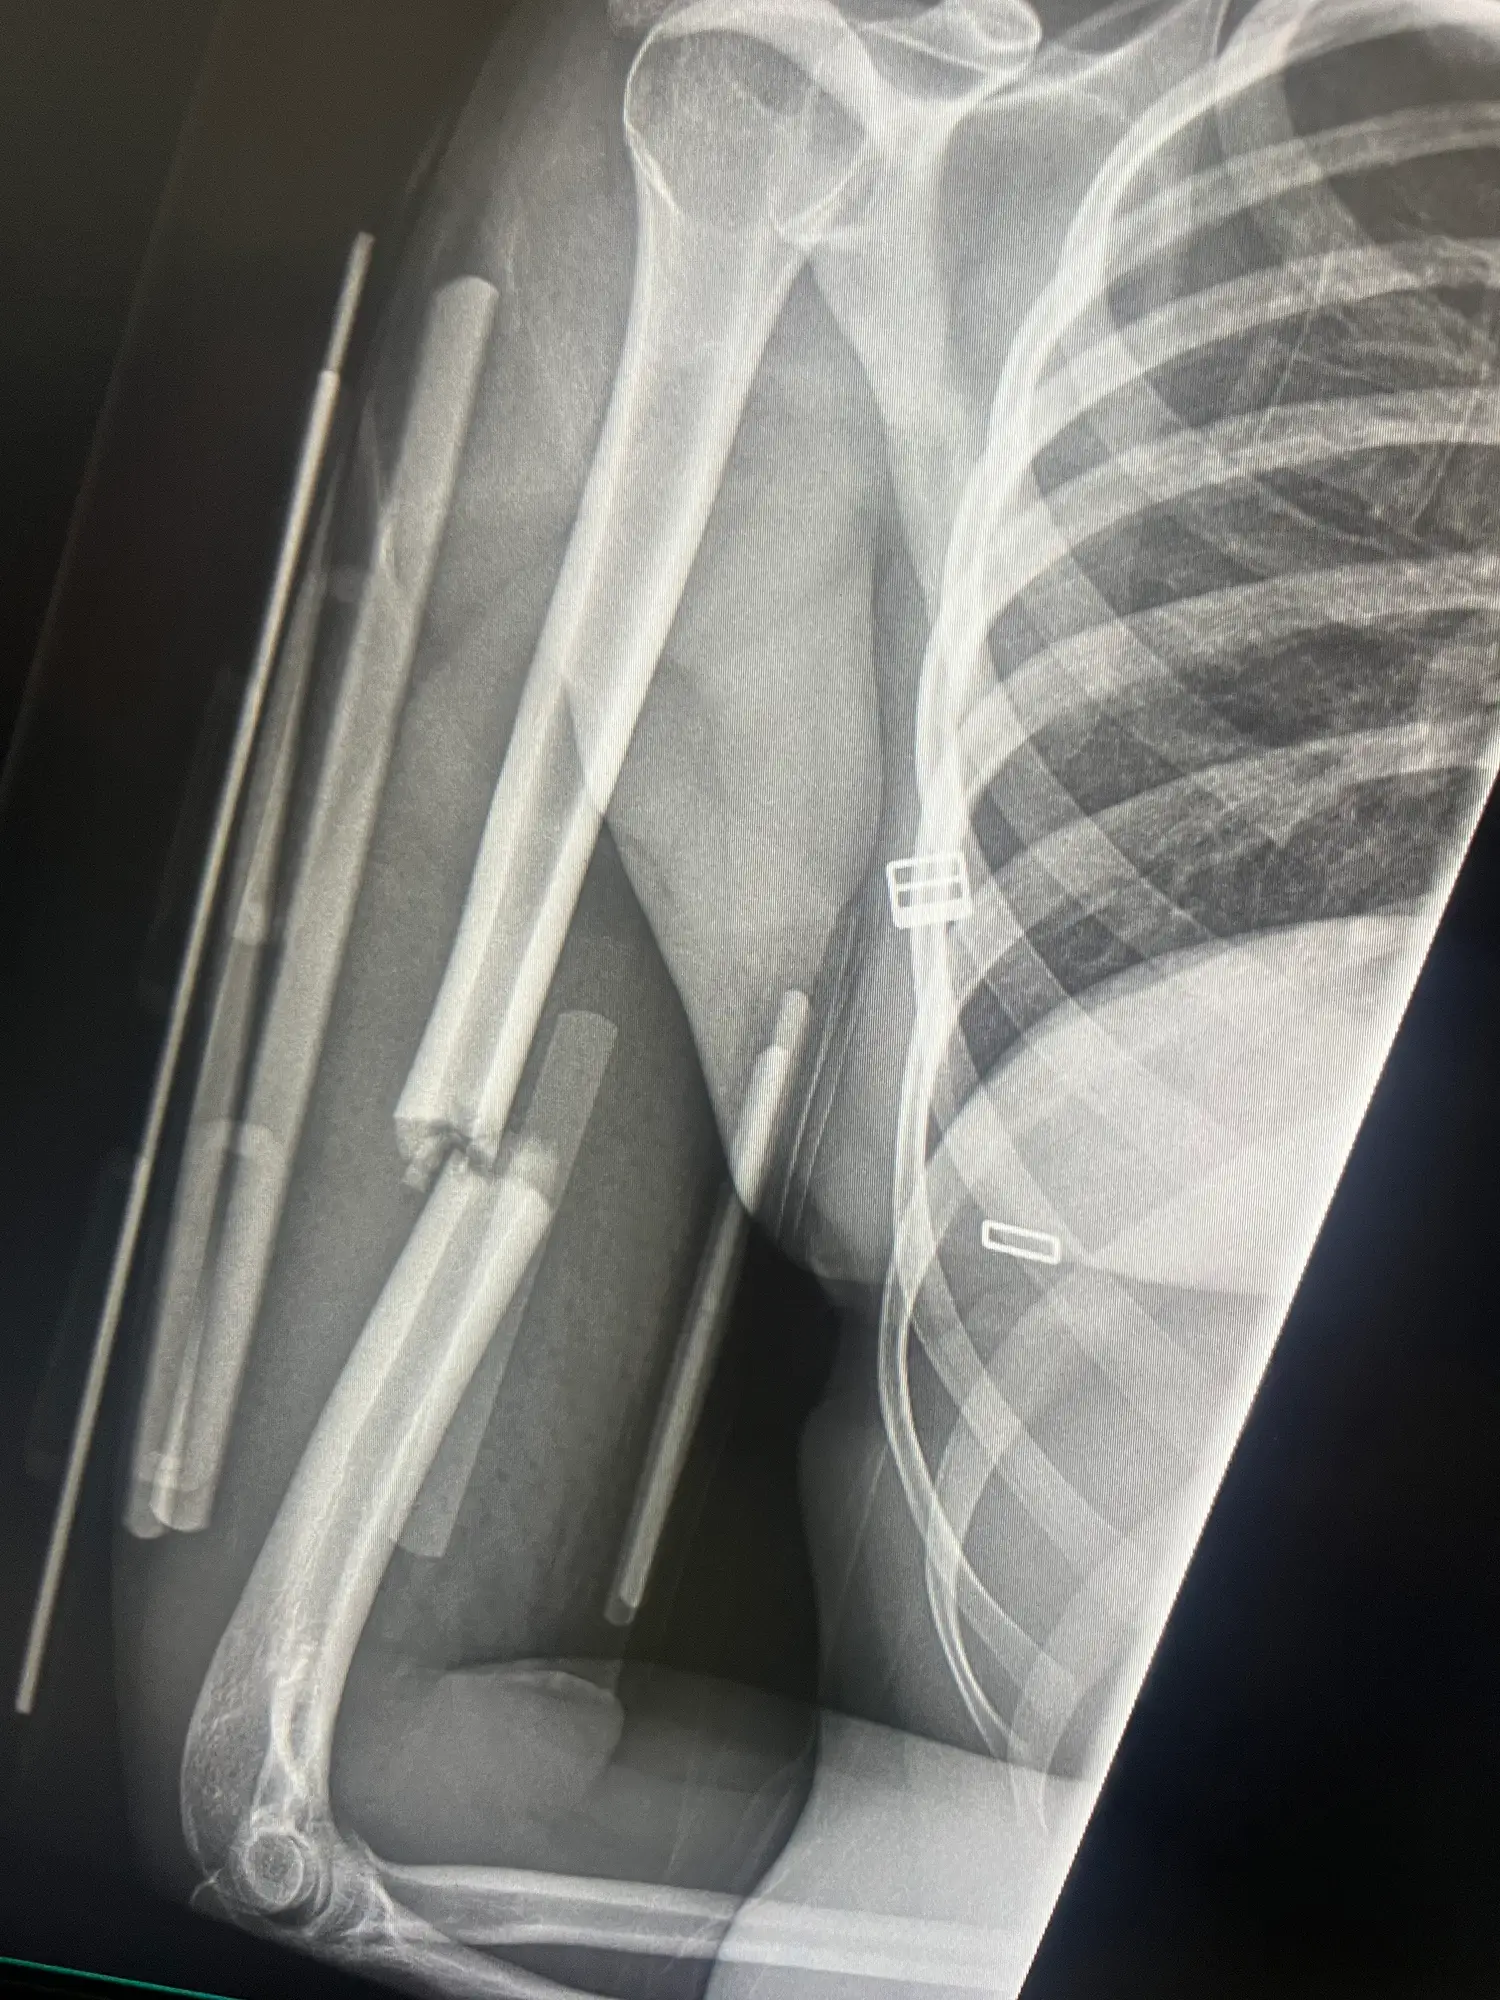

Your likelihood of ending up in A&E with a broken leg is something which you inherit from your parents, with Dr Hussain saying inherited traits like bone density or the way in which your body processes calcium are crucial to whether or not you're more likely to break a bone.

"Bone strength is largely inherited. That includes how dense your bones are, how well your body processes calcium, and even how your skeleton is built," he said.

"Some of us are naturally more prone to thinner bones — and those can snap more easily under pressure."